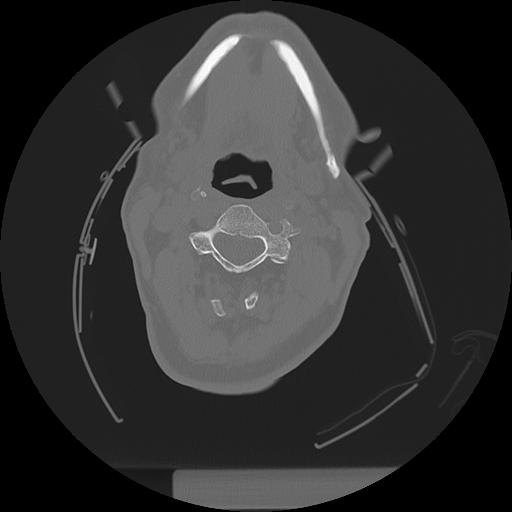

11 HUESO,,Axial,2.0,HUESO,,